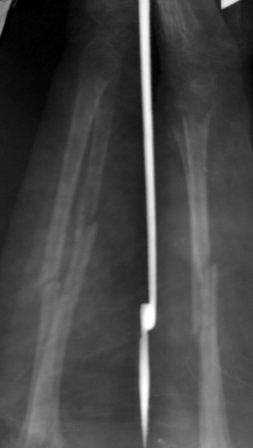

Ложный сустав костей предплечья

Пациентка 49 лет, по поводу перелома обеих костей предплечья оперирована в марте месяце « и/м остеосинтез спицами»,

через 4 месяца спицы удалены , антибиотикотерапия и фиксация гипсовой повязкой продолжена, но, учитывая что образуются ложный сустав, госпитализирована.

Повторно открывать зону перелома никак не хочется, учитывая р-картину! А что если закрыто рассверливать к/м канал ( как при БИОС), и КДО аппаратом Илизарова?

Уважаемые коллеги помогите советом! Извиняюсь за плохое качество р-снимков!